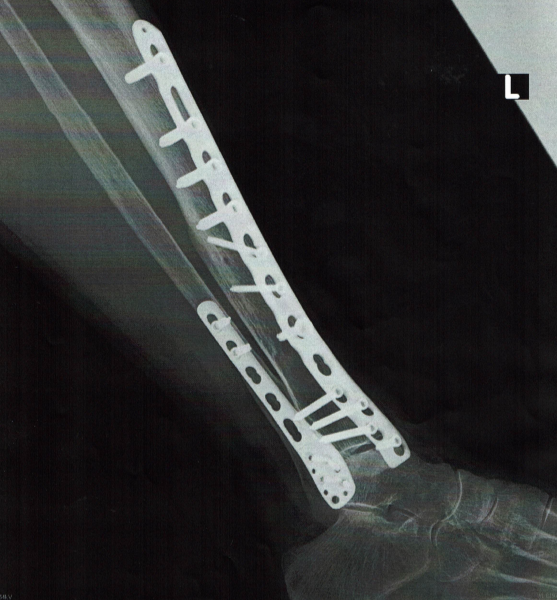

右の写真は中学2年生がバスケットボールの練習中、リバウンド着地の際に発症し、連絡があって自宅に訪問した際の写真です。

骨折を疑い、友人のスポーツ整形外科医に紹介した症例です。

脛骨粗面のはく離骨折でした。

患者様への情報提供として、手術の有無に関するメリット・デメリットをご説明し、疑問不安をお聴きして、患者・患者ご家族のご希望で手術による固定をおこなった症例です。

術後、帰宅されてからは担当医と密接に連絡を取りながらスポーツ復帰までアスレティック・リハビリテーションでの対応をさせて頂きました。

歩行、ジョギング、ランニング、ダッシュと徐々にストレスを上げていった際、ビデオによる画像チェックにより、確認しながら復帰に向けてのトレーニングも行ないました。

上記の脛骨骨折写真のように、骨折であれば五つの症状が発症します。軽度のケガであれば痛みで動けないけれど腫れ、熱は発症しない場合もあります。痛めた原因がハッキリしていると、症状の改善は保険施術となります。